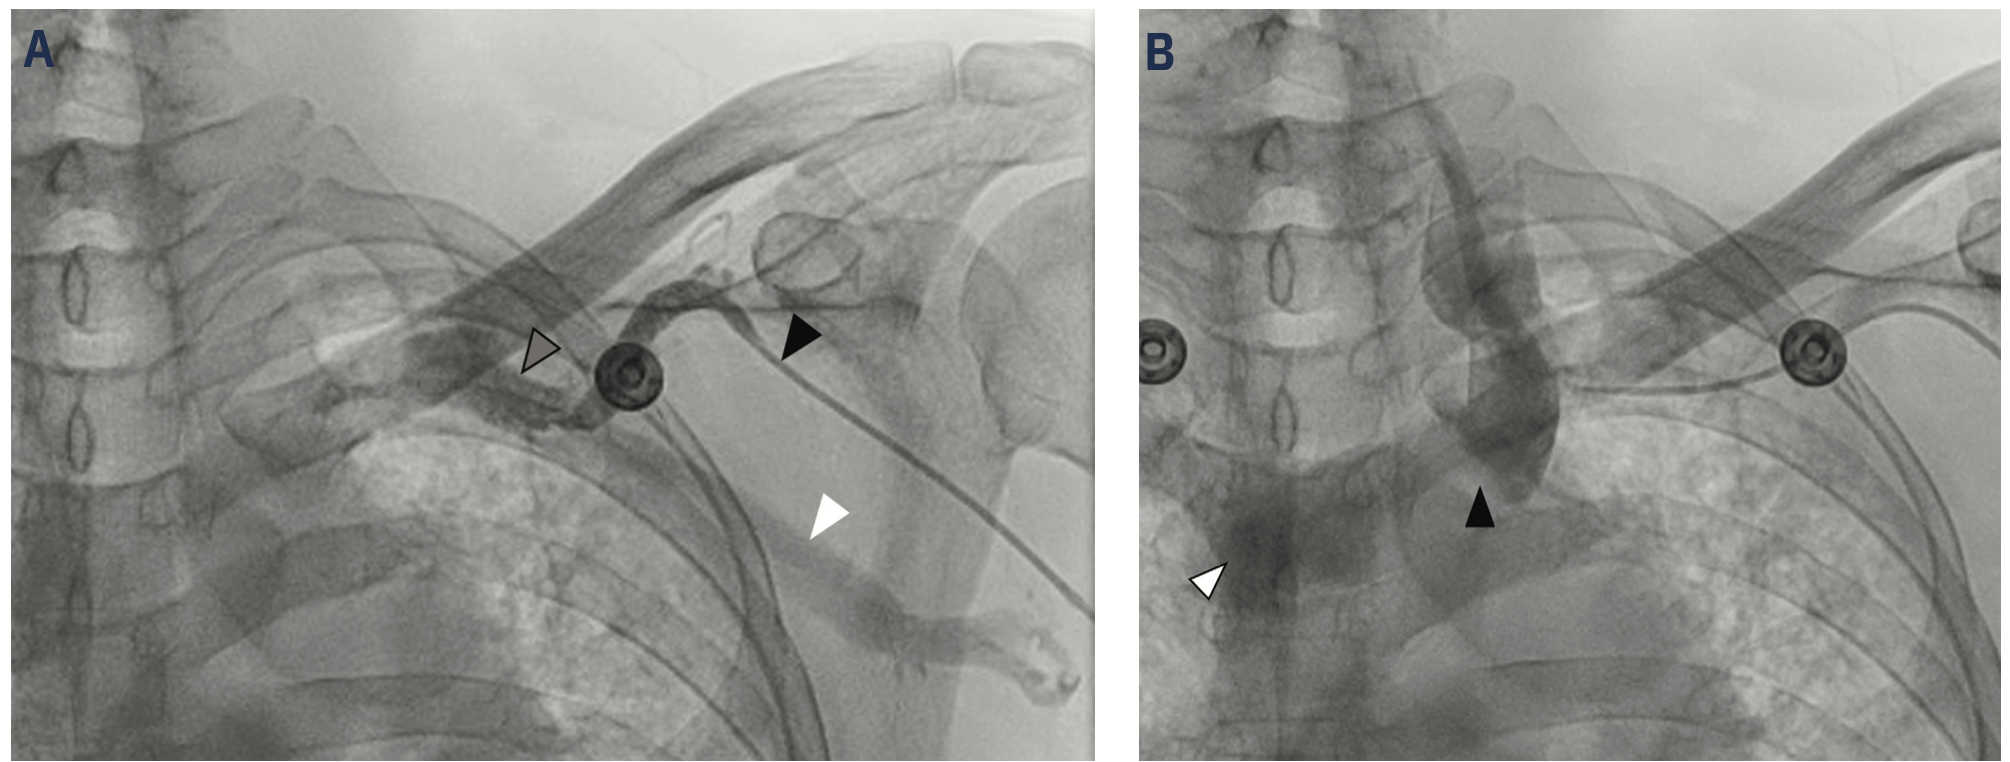

On the day of procedure, the patient had no chest pain. He was on his chronic home requirement of 4 liters of oxygen. Physical exam revealed bibasilar dry crackles, no pericardial rub, no peripheral edema, and no elevation of jugular venous pressure. A RHC was performed with ultrasound-guided right brachial venous access. Despite successful entry into an ultrasound-documented brachial vein, the guidewire could not be advanced >10 cm without meeting resistance. Several similar attempts with adjacent veins also failed. Proximal vein images show diffuse and severe narrowing of the right brachial medial veins (Figure 4A) and were assumed to be a consequence of prior PICC placement. Left brachial vein access was then attempted and was also noted to be difficult due to severe venous narrowing (Figure 4B), but access was eventually achieved via the cephalic vein using the assistance of an angioplasty guidewire. The 5 French (F) balloon-tipped catheter was advanced to the subclavian vein also with some difficulty, requiring a guidewire to facilitate passage, and angiography showed a large axillary vein on injection of contrast into the brachial vein. Both the internal jugular vein and superior vena cava (SVC) were extremely large in caliber with turbulent angiographic flow. Further advancement of the balloon catheter required an .014-inch guidewire (Figure 5A-B). The guidewire preferentially moved into sites one would expect of the azygous and internal thoracic veins. Finally, after traversing the complex subclavian vein, hemodynamic measurements were obtained with the 5F balloon-tipped catheter. Blood oxygen saturations with hemodynamic recordings showed right heart hemodynamics and cardiac output that were normal (Table 1). There was an inability to advance the balloon catheter safely to the pulmonary capillary wedge pressure position, despite using a guidewire, due to strong proximal resistance, so this measurement was deferred. After collecting sufficient hemodynamic data to determine transplant candidacy, the 5F catheter and sheath were removed. Hemostasis was obtained using manual compression. There were no postprocedural complications.